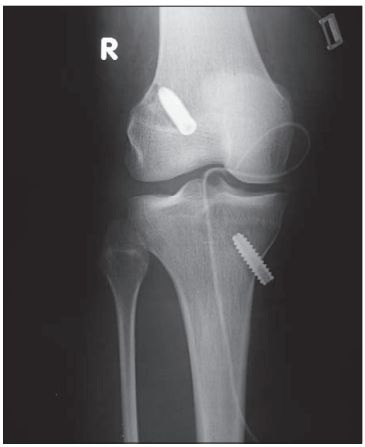

Migracja śruby piszczelowej poza kanał kostny

W 8 tygodniu po zabiegu pacjentka zgłosiła się do poradni Kliniki skarżąc się na ból i obrzęk okolicy przednio-przyśrodkowej podudzia, w sąsiedztwie otworu kanału piszczelowego. Objawy pojawiły się przed 3 dniami i były związane ze zwiększeniem obciążenia w ćwiczeniach aktywnego wyprostu i intensyfikacji rehabilitacji.W kontrolnym badaniu RTG zaobserwowano migrację śruby piszczelowej poza kanał kostny. Śruba była wyczuwalna palpacyjnie w tkance podskórnej. Zdarzenie to nie wpłynęło na stabilność stawu. Testy kliniczne pozostały ujemne a pacjentka nie zgłaszała „uciekania” kolana. Śruba została usunięta operacyjnie, a pacjentce zalecono wstrzymanie się od nasilonej aktywności fizycznej przez miesiąc.